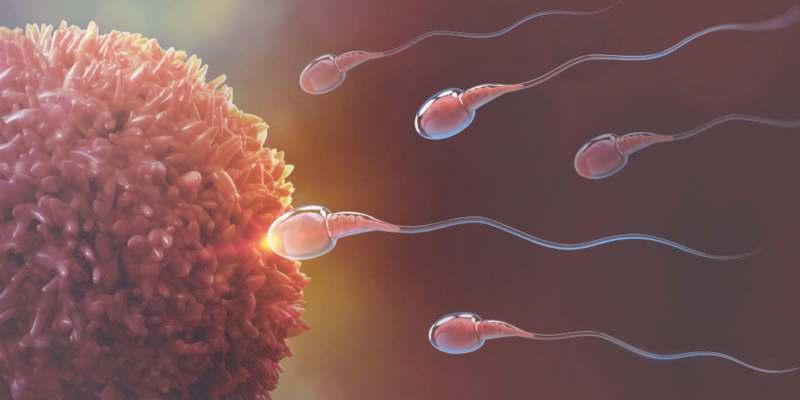

ASPECTOS BIOLOGICOS DE LA REPRODUCCIÓN HUMANA

Desde el nacimiento del ser humano claramente definidos sus organos sexuales (caracteres sexuales primarios). Con el trascurso de los años, al llegar a la pubertad el hipotálamo atúa sobre glándula hipófisis dando lugar a que las hormonas actúen tanto en los testículos en el caso de los hombre y los ovarios en caso de las mujeres llevando acabo la produccuón de espermatozoides y de hormonas. Su función se haxe evi dente durante el coito o la masturba ción, en los cuales representan variaciones en tamaño y posición de acuerdo a los niveles de exi tación.

Durante la excitación sexual los espermatozoides salen del epidídimo a través del conducto deferente. Allí se mezclan con el líquido producido en las vesículas seminales y la próstata para formar el semen.

Hay que destacar que el semen ayuda a nutrir a los espermatozoides y a la vez ha transportarlos

* Los testiculos: Son glándulas que producen espermatozoides y a la vez producen hormonas son células reproductoras.

* El epididimo: Este es un conducto enrollado que alberga a los espermatozoides mientras maduran.

* El conducto deferente: Transporta el esperma desde el epidídimo hasta el pene.